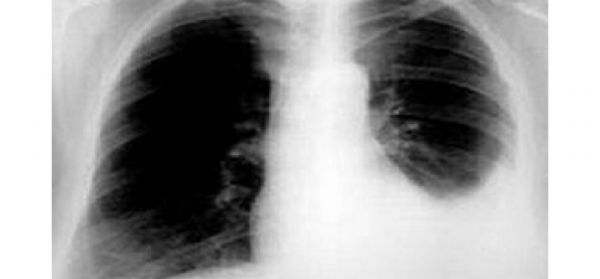

Hình ảnh tràn dịch màng phổi toàn bộ bên pbổi trái (các cơ quan trung thất bị đẩy hoàn toàn sang phải)